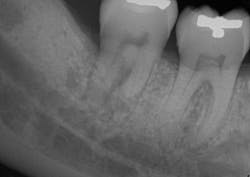

A clinical periodontal and radiographic assessment is completed. Although there is moderate bone loss in all four quadrants, his periodontal status is stable with the exceptions of Nos. 18 and 31 distal (figures 1 and 2). Both areas reveal direct distal probing depths of at least 10 mm and radiographic infrabony distal defects.

Figure 2: No. 31

The patient returned after two weeks for a postoperative check of No. 31 and had a maintenance visit at three months post-op. At the three-month mark, the Visual-SRP area was evaluated for results. The pocket depth had resolved to 4 mm without signs of inflammation. A periapical radiograph of the area suggested bone remineralization in the site of No. 18 distal (figure 3). No. 31 was required to heal for six months and was not assessed until that time. At the six-month mark, the patient returned for another maintenance visit. The surgical area was measured, and the pocket depth had resolved to 4 mm without signs of inflammation. The periapical radiograph of No. 31 distal revealed the vertical defect was repaired, and new bone formation was evident (figure 4).

Figure 4: Periapical radiograph of No. 31 distal shows a repaired vertical defect and new bone formation, six months after treatment with periodontal pocket reduction surgery and bone regenerative materials